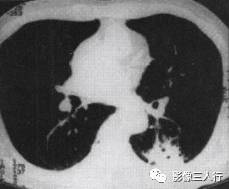

胸部CT图像显示,在含气少的致密肺的背景上见到含气的支气管,表现为两种形态: ①在大片肺实变病灶内的细条状空气密度影;②直径Imm的小泡状空气密度影,连续的几 个层面都能出现(图2、图3)。该征象表明:①近侧气道通畅;②肺泡内的空气经吸收(肺不张)或取代(肺炎、肺癌),或两者综合而消失。通畅含气的支气管在肺泡实变高 密度区内表现为管腔内低密度充气轮廓。